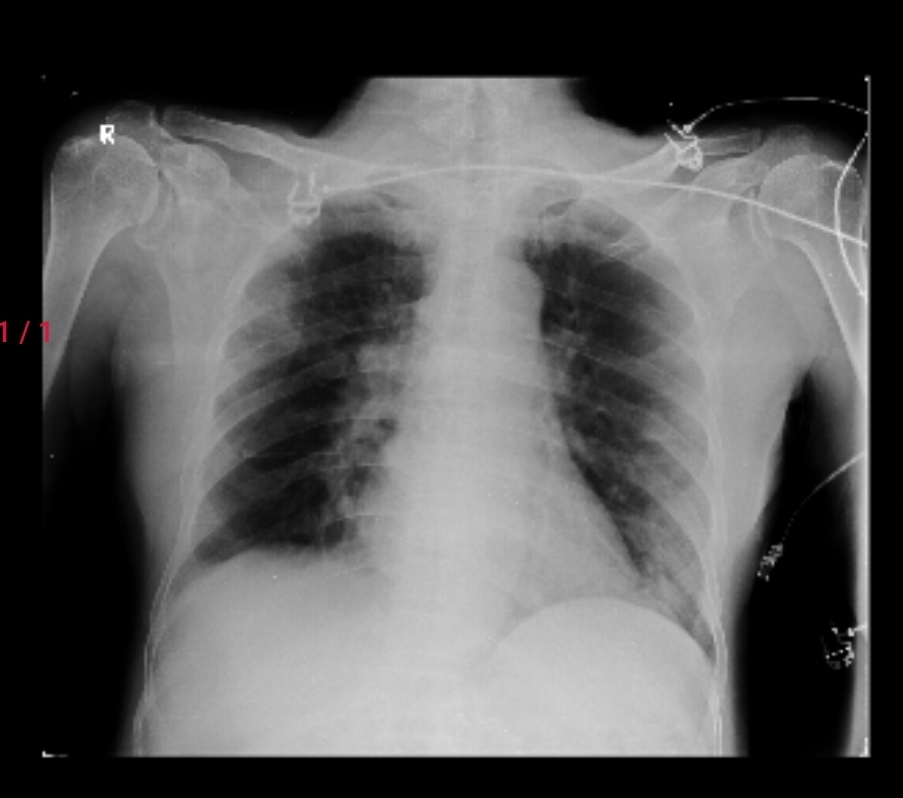

CHEST X.RAY ON 21/11/2024

CHEST X.RAY ON 24/11/2024